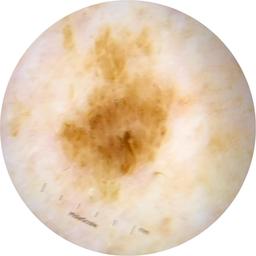

Field Value

acquisition_day 229

age_approx 70

anatom_site_1 Head and neck

anatom_site_general head/neck

concomitant_biopsy False

diagnosis_1 Benign

diagnosis_confirm_type single image expert consensus

family_hx_mm True

image_manipulation instrument only

image_type dermoscopic

lesion_id IL_5016640

patient_id IP_7825931

personal_hx_mm True

sex male